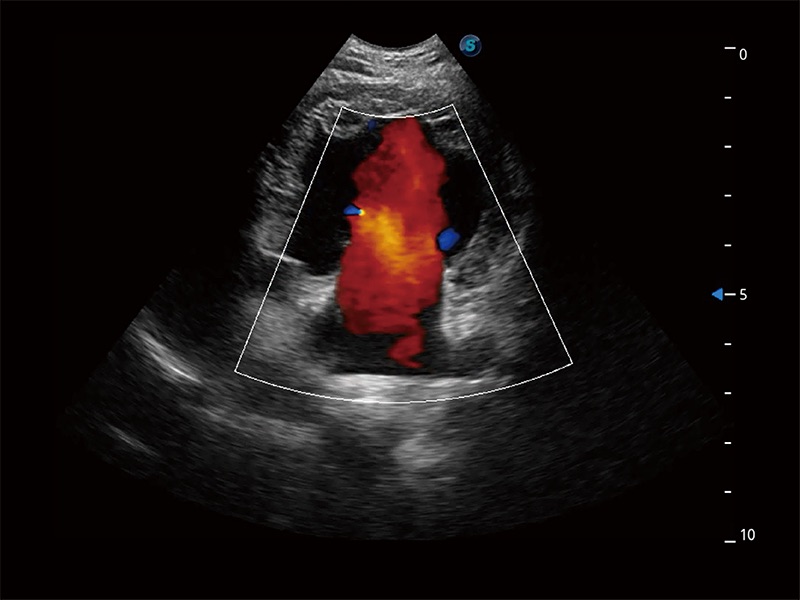

• Bright Flow 立体血流成像

在传统二维血流成像的基础上,呈现血流的立体感,具有动感的生命力之美。即便是微小的血管也能轻松应对,提高了血流的视觉敏感性。

(犬)胎儿主动脉弓立体血流

(犬)二腔心血流